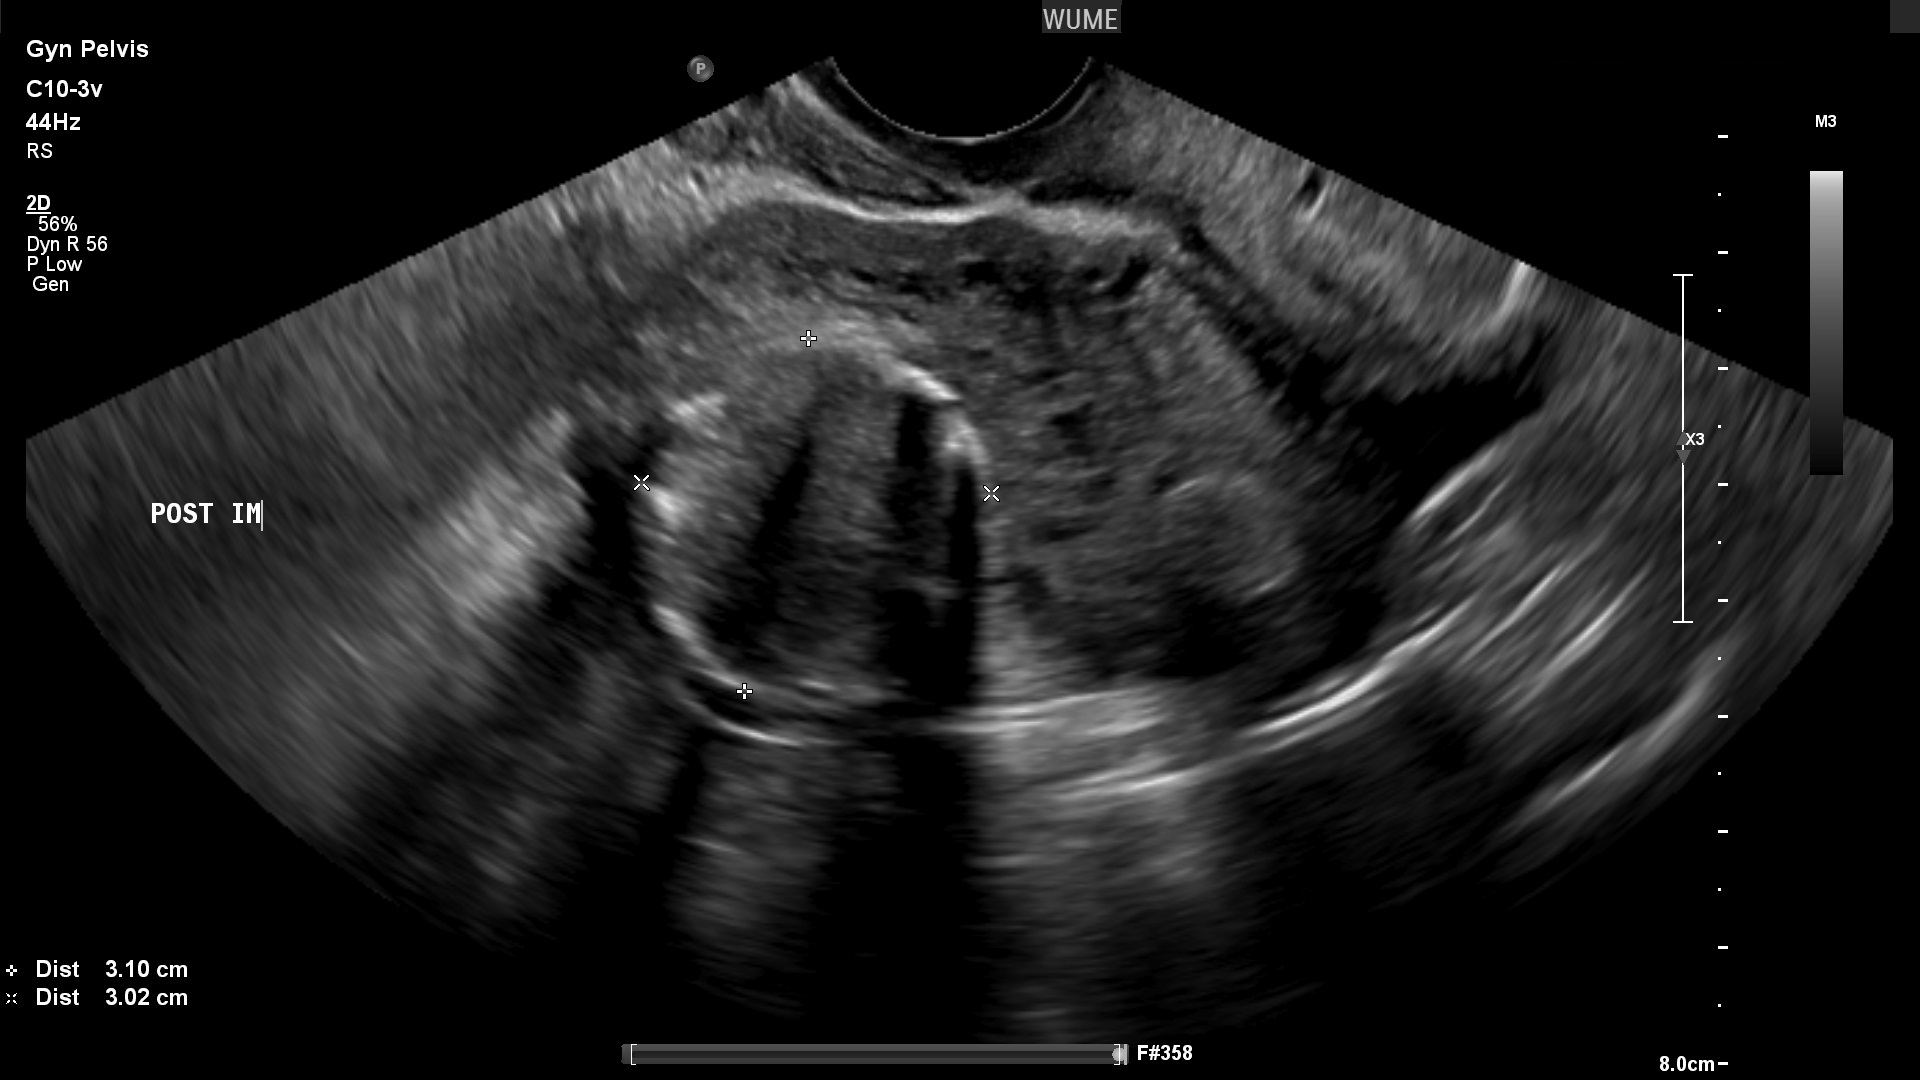

فیبروم ها

فیبروم ها تومورهای رایج عضله رحم هستند و تقریبا همیشه خوش خیم هستند. آنها گاهی اوقات باعث بی نظمی قاعدگی می شوند و ممکن است تحت نظر باشند زیرا می توانند در طی چند سال به طور قابل توجهی رشد کنند. آنها ممکن است رحم را بزرگ کنند و یک "توده" احساس یا فشار لگن ایجاد کنند.